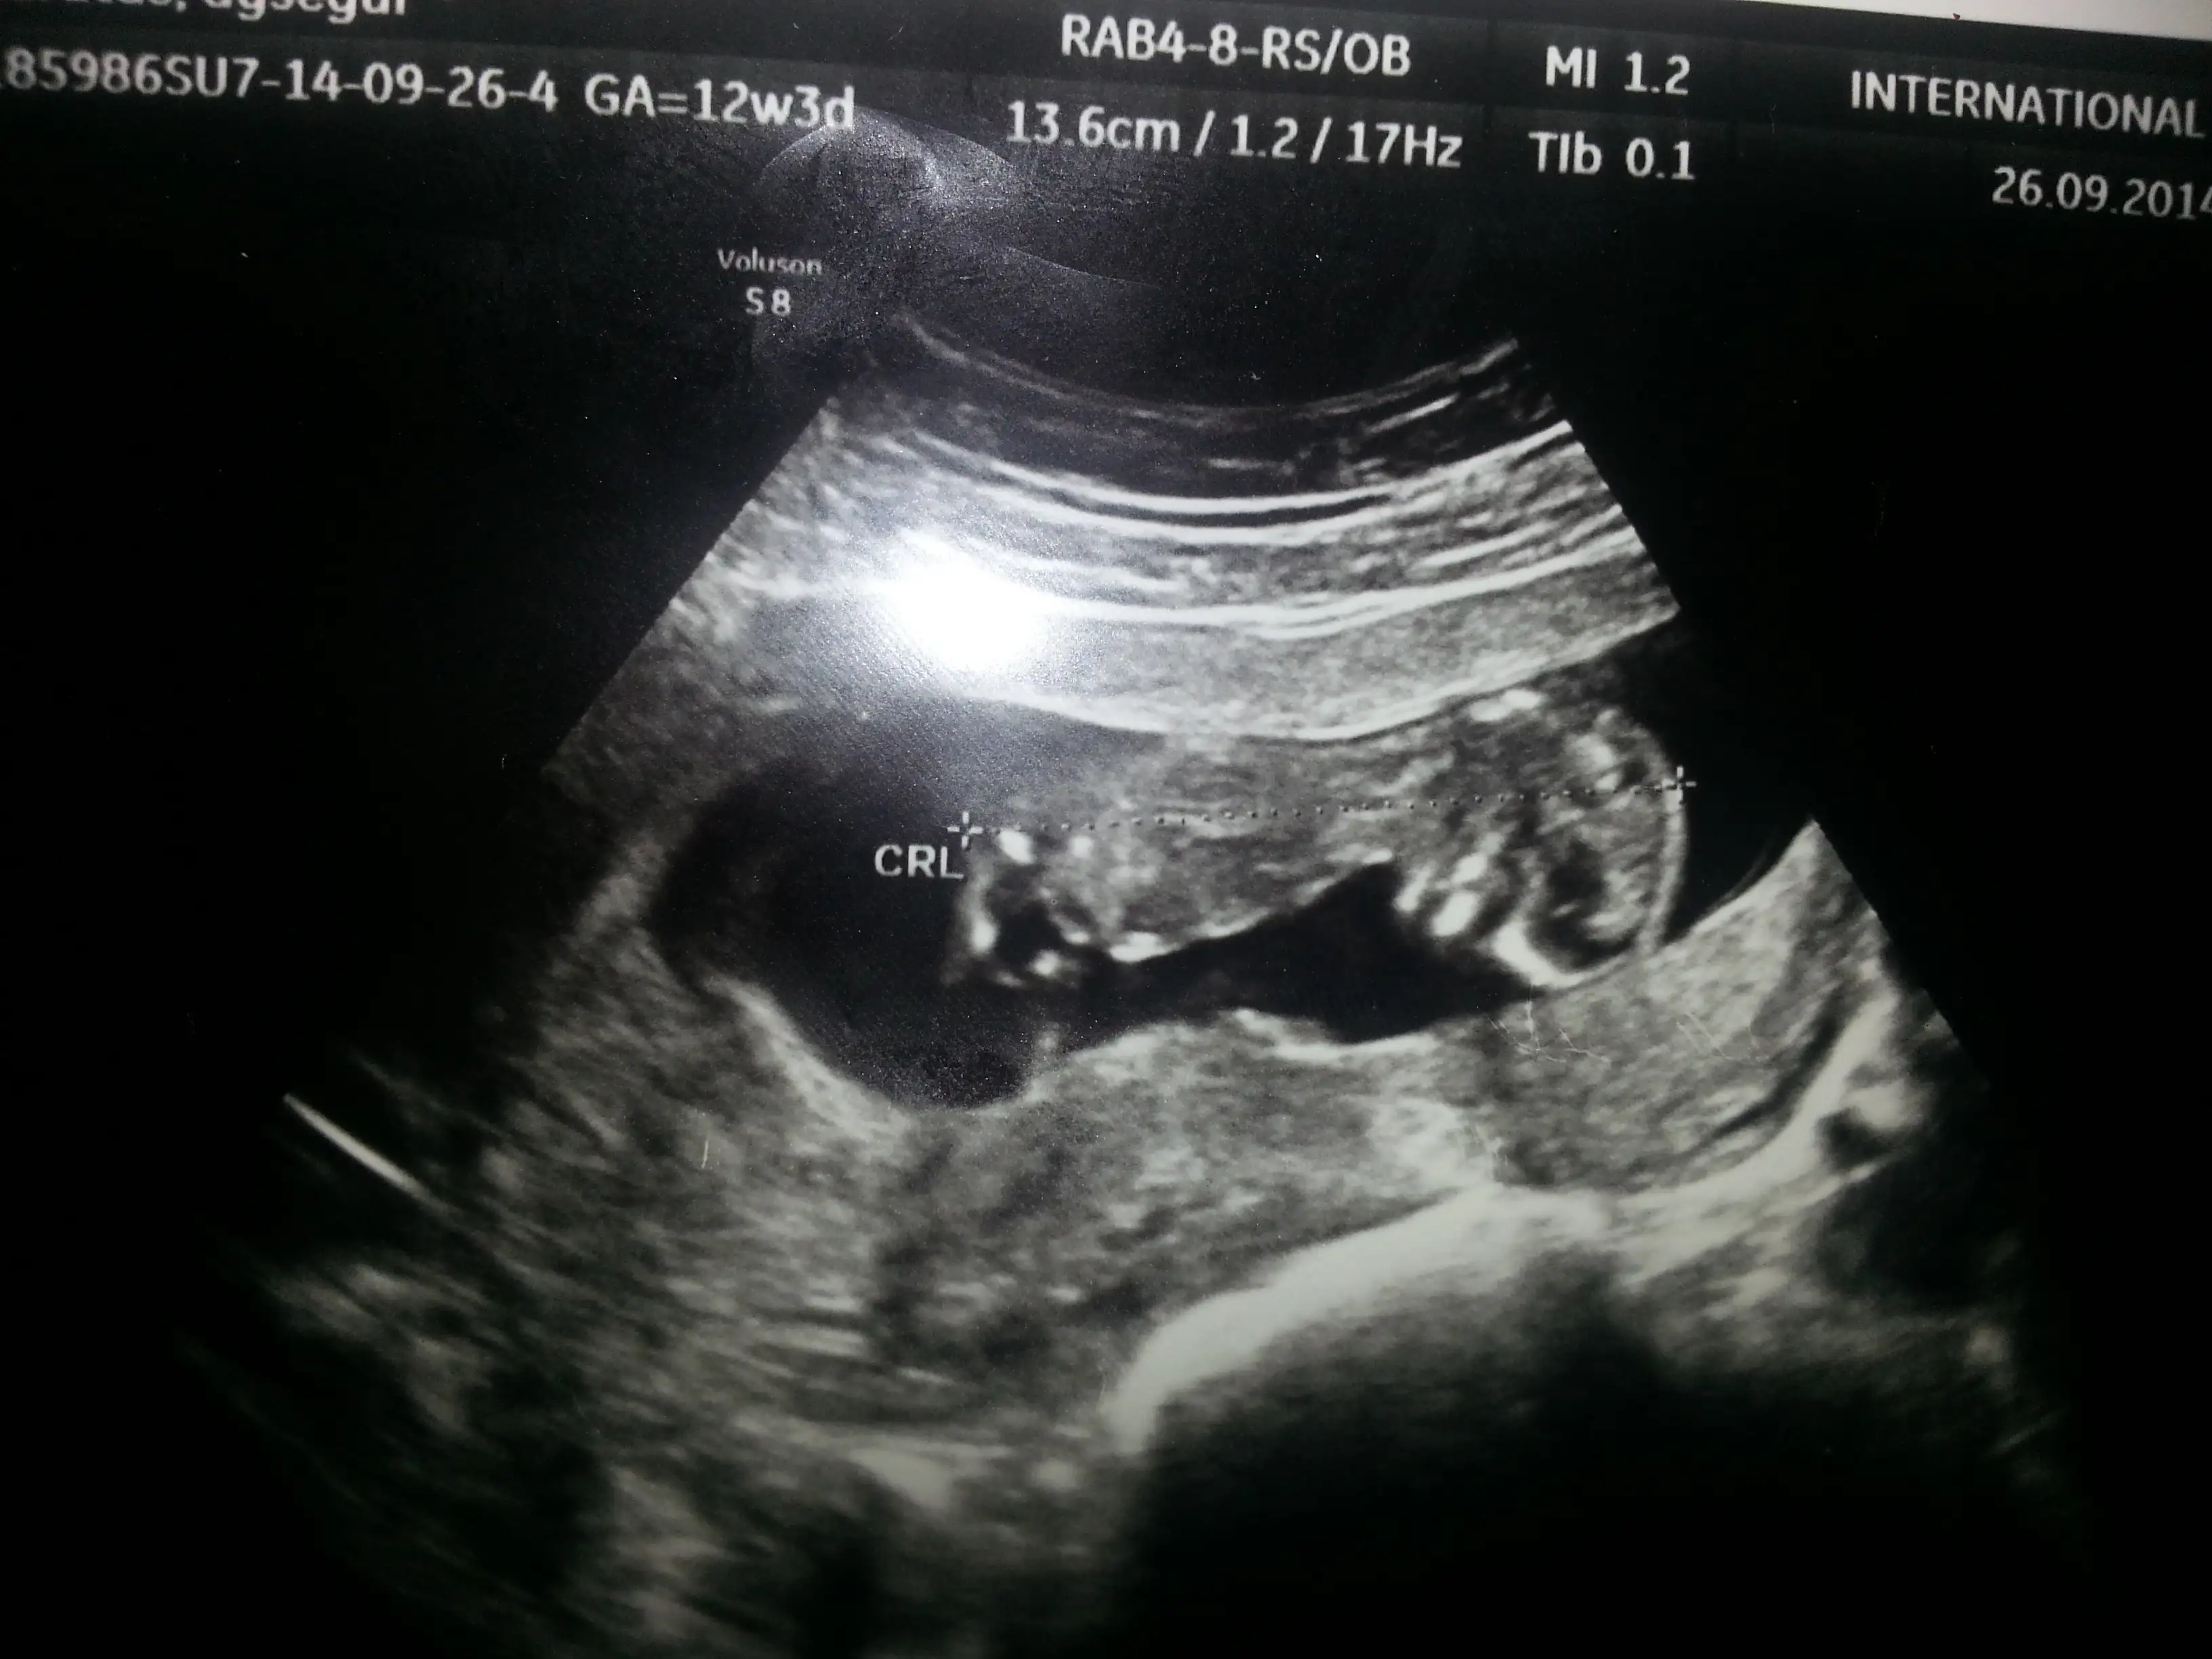

Kizlar 12haftaligim bi yorum yapabilirmisiniz? Cok merak ediyiruz simdiden cok tesekkurler

20140930_194446.webp

Kızlar benim bebiş 12haftalık oldu dr cinsiyetıni söyleyemedi anlayan arkadaşlar yorum yapabilirmi

• 20140930_182213.webp

20140930_182213.webp

101,4 KB · Görüntüleme: 184